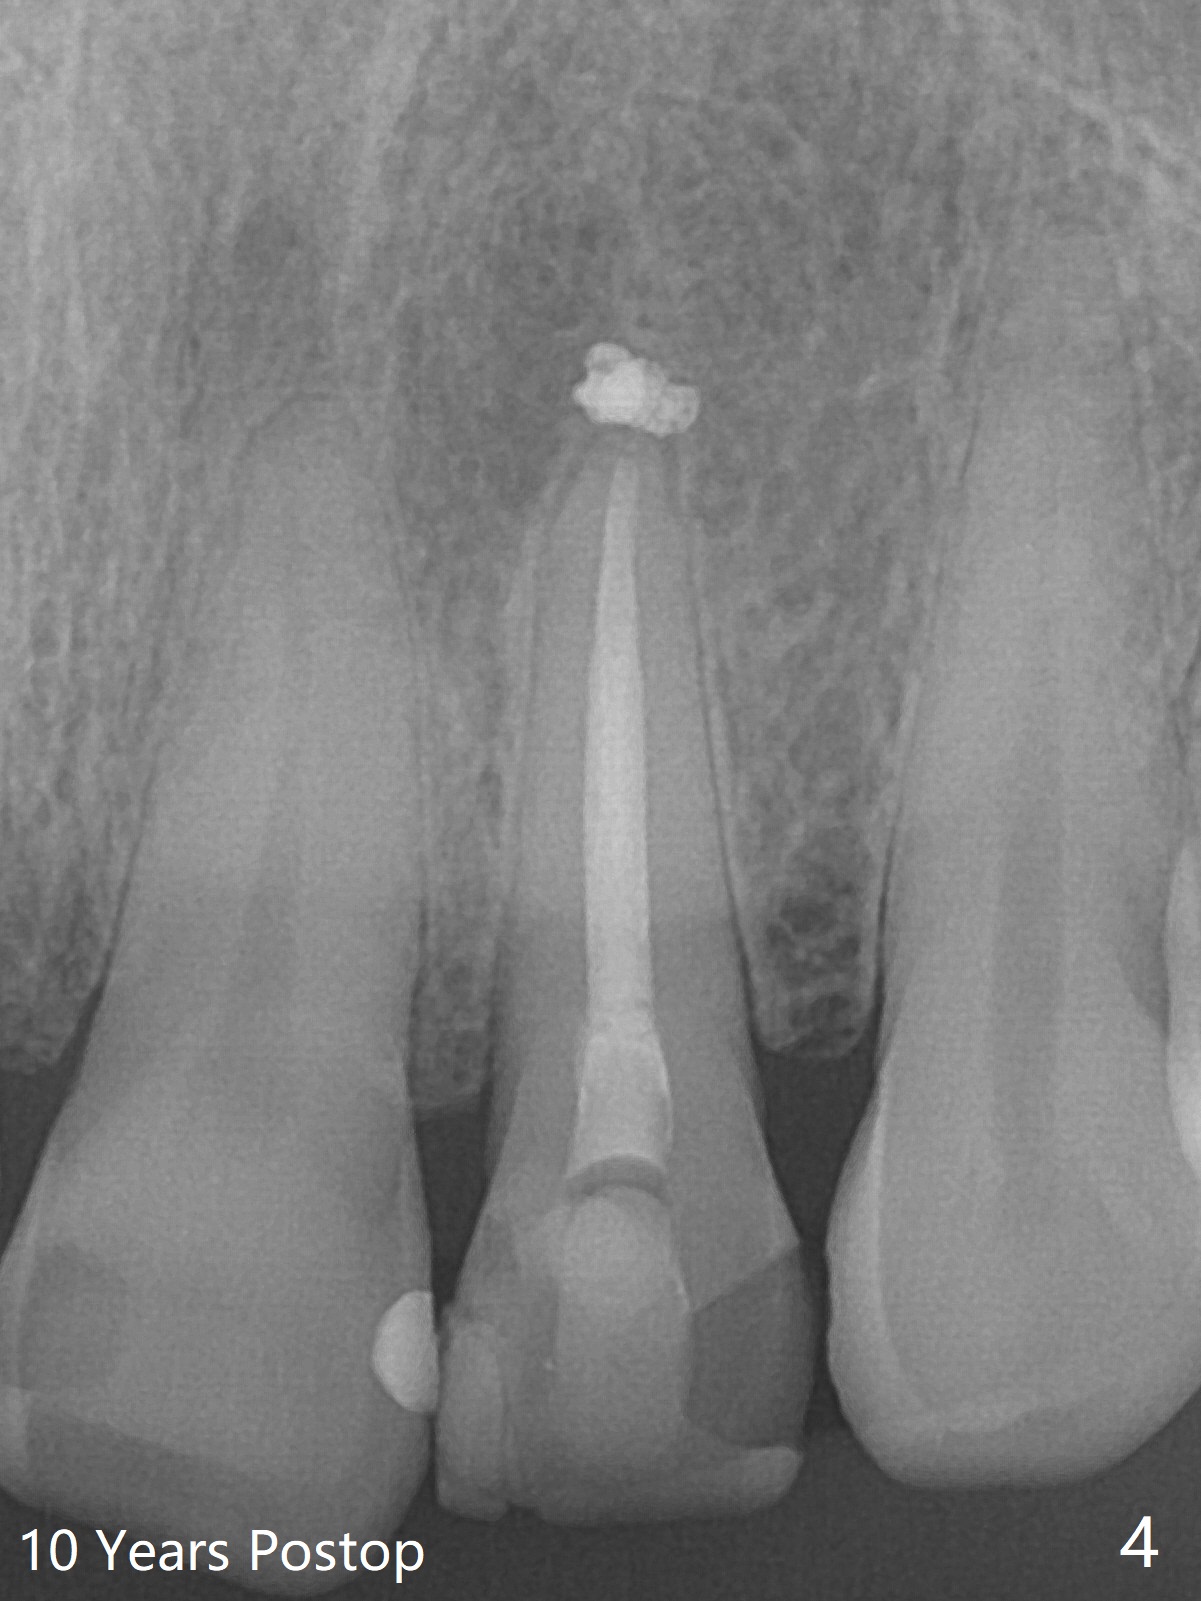

10 Year Follow-Up for RCT

A 47-year-old woman with multiple restoration has PARL at #10 (Fig.1 *). RCT is done with paste leakage (Fig.2). PARL reduces and disappears 2.5 and nearly 10 years postop (Fig.3,4).